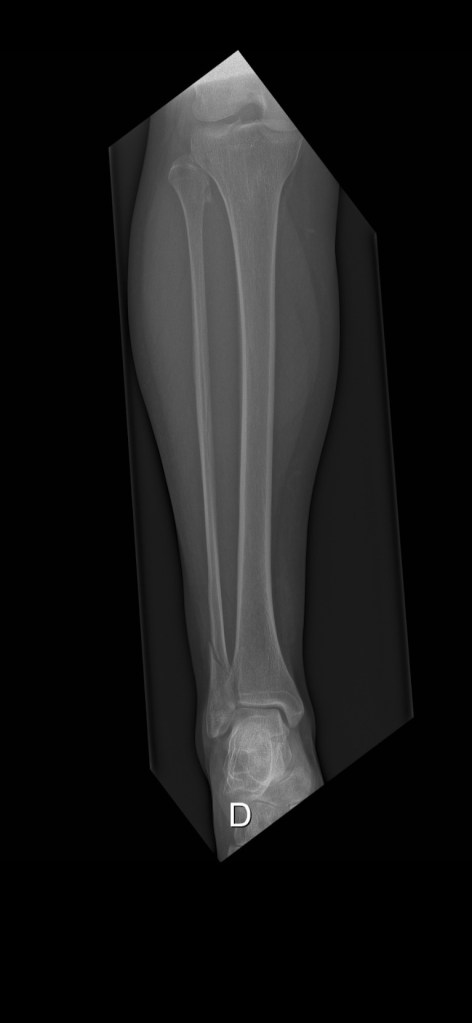

Ich habe einen neuen. Einen sogenannten Gehgips. Aus Plastik und zum Auftreten. Mit Anpassung vom Chef-Orthopäden und Röntgenbildern, die mit Auftreten im Stehen gemacht wurden. Allerdings plagen mich Kopfschmerzen des Todes. Als Trostpflaster haben die Kids gekocht – Mamas Lieblingsessen: Vol-au-vent mit Fritten und Königinpastete, Bouchée à la reine. Das Vol-au-vent gibt’s von Lidl in Belgien im Glas. Das ist hier das Ravioli (ich hasse Ravioli) für Leute, die schnell kochen müssen. Lecker und ein Trostpflaster.

Verband auf belgische Art- Gips Teil 3

Die Herrschaften in der Notaufnahme waren wirklich sehr nett. Haben mir erklärt, dass eine aufblasbare Schiene nicht so sinnvoll wäre, wie ein oldschool Gips. Mit Verband. Okay. Die sind immer sehr freundlich da und ich meckere ja nicht. Er ist nur sooo schwer und das ist echt … sch….

Der Gips- Teil 2

Ich sitze im Bett, weil schon das kleinste Bewegen meines Gipsbeins zuverlässig zur schmerzhaften Grundsatzdiskussion führt. Also bleibe ich liegen. Aus reiner Vernunft – und weil Tramal allein keinen Heldenroman schreibt.